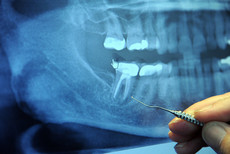

Wird der Zahnschmelz zerstört, ist dies anfangs nicht zu bemerken, schreitet der Abbau jedoch fort, sind schmerzempfindliche und gelblich-dunkel verfärbte Zähne die Folge. Immer wieder hört man in den letzten Jahren von reparierenden Zahncremes, die gegen diese Schäden helfen sollten. Risse und Löcher sollen gekittet werden, die Zähne sollen weniger schmerzempfindlich sein und wieder heller werden. Allerdings ist es zweifelhaft, dass die Versprechen der Werbung tatsächlich eingehalten werden können. Zwar konnte in einer Studie nachgewiesen werden, dass durch die Nutzung der Reparaturcreme Speichel vermehrt gebildet und Säure neutralisiert wird, dies sei allerdings ebenso mit herkömmlicher Zahncreme zu erreichen. Außerdem konnte bisher nicht bewiesen werden, dass diese Mittel zu helleren Zähnen führen.

Ein Grund, warum es beim Menschen zu einer vermehrten Abtragung von Zahnschmelz kommen kann, liegt beim falschen Putzen der Zähne. Wie die Universität Witten/Herdecke im vergangenen Jahr in einer Studie belegen konnte, putzen zwei Drittel aller Deutschen ihre Zähne falsch. So sollten Erwachsene keine kreisenden Bewegungen beim Putzen ausführen und sich mehr auf diese Tätigkeit konzentrieren. Ein zu starker Druck auf die Zähne kann zudem den Zahnschmelz gefährden.

Viele Erwachsene leiden nicht nur unter Karies und fehlendem Zahnschmelz, sondern auch unter verfärbten Zähnen. Auch hier kommen Spezialzahnpasten oft zum Einsatz. Sind die Zähne durch Kaffe, Rotwein, Tee oder Nikotin leicht verfärbt, können diese Pasten durchaus helfen, wie Stiftung Warentest 2011 feststellte. Gibt es allerdings Probleme mit der Zahngesundheit, sollte man mit einer professionellen und regelmäßigen Zahnreinigung beim Zahnarzt vorsorgen. Vielen Menschen ist dies aber zu teuer, da sie in den meisten Fällen nicht von der Krankenkasse gezahlt wird. Informationen zur privaten Zahnzusatzversicherung können helfen herauszufinden, wie man mit der passenden Versicherung diese Kosten umgeht.